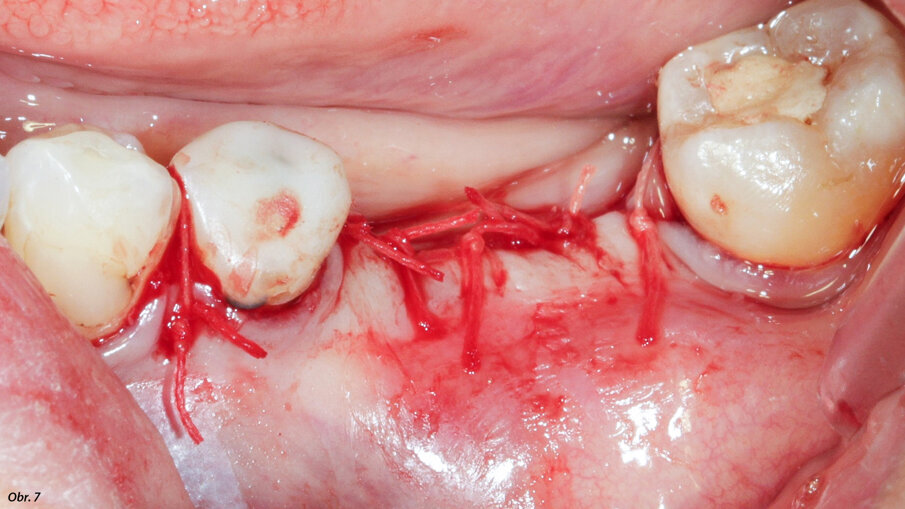

K sešití bylo použito rychle vstřebatelné splétané vlákno č. 4/0.